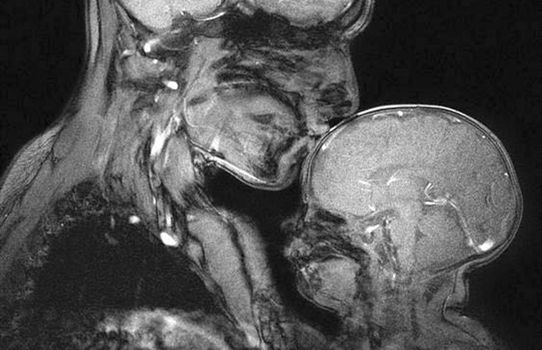

Holding her two-month-old baby boy Perry, Saxe curled up inside the tube of a 3 Tesla magnetic resonance imaging scanner and the image was taken.

Writing in The Smithsonian, Saxe said: “No one, to my knowledge, had ever made an MRI image of a mother and child. We made this one because we wanted to see it.”

The resulting image is as awe-inspiring as it is beautiful, a stark reminder of how delicate the human body really is.

“Some people look at it and see mostly the differences: How thin his skull is, how little space there is between the outside world and his brain. It’s just this very fragile, very thin little shell,” Saxe said.

“On the other hand, you can look at it and see how similar it is to his mother’s brain. How close in size — so much closer in size than his hand is.

To some people, this image was a disturbing reminder of the fragility of human beings. Others were drawn to the way that the two figures, with their clothes and hair and faces invisible, became universal, and could be any human mother and child, at any time or place in history. Still others were simply captivated by how the baby’s brain is different from his mother’s; it’s smaller, smoother and darker—literally, because there’s less white matter.